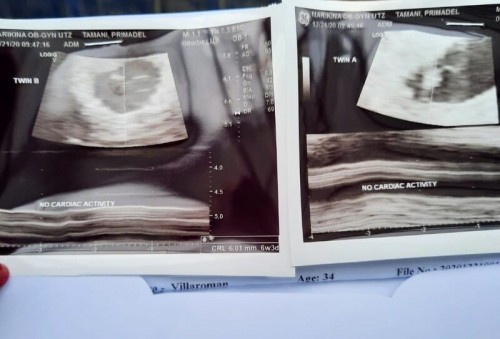

No heartbeat at 7 weeks

Nagpatransv ako today im on my 7th week with my twins. First time mom with myoma, heavy weight din ako and a smoker pero i stopped all my vices when i learned na im pregnant with twins. Followed all instructions and vits,duphaston 3x a day.Sobrang worried ko kasi ung ob na nagtransv (not my ob) said na hindi daw maganda tong pinagbubuntis ko kasi walang heartbeat din. Sobrang iyak ako ng iyak... ngayon waiting ako sa update ng OB ko tlga for online consulatation . Anyone who expereinced this? Advise pls... #firstbaby #1stimemom #pregnancy #advicepls